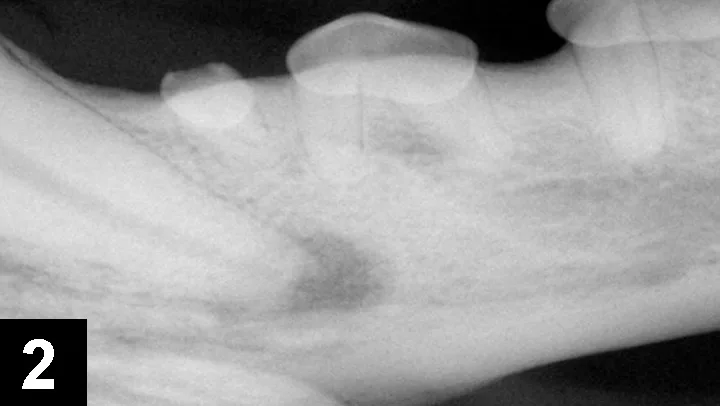

Approximately 25% of dogs are presented with one or more fractured teeth, and 10% have a complicated crown fracture indicating the pulp canal is exposed (Figure 1).4-6 Once exposed to the oral cavity, the canal pulp becomes contaminated, infected, and necrotic, eventually resulting in periapical infection and pain. An oral examination of the patient while under general anesthesia can detect exposed canal pulp; a dental explorer will stick or drop into the open pulp. If open pulp is identified, intraoral radiographs are required to assess the periapical tissues (eg, periapical lucency, root resorption) and the size of the pulp canal (eg, may be wider compared to the contralateral tooth; Figure 2). Necessary treatment options for a pulp-exposed, infected tooth include root canal treatment or surgical extraction.

Left mandibular canine tooth root (tooth 304) that had a complicated crown fracture. A periapical lucency, external inflammatory apical root resorption, and a relatively widened pulp canal are present, indicating the tooth has been dead and infected for months. The chronically exposed pulp results in periapical infection and inflammation.